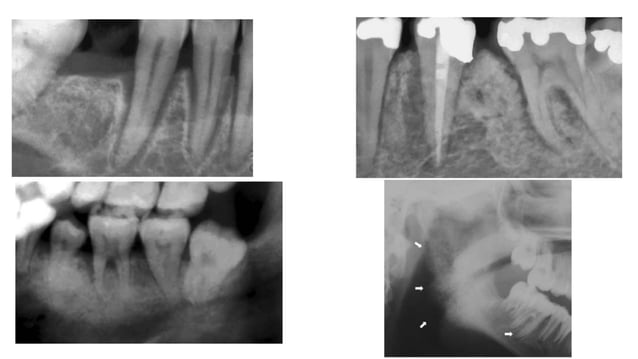

Widening Of PDL PPT

Chest X Ray Mediastinum Images

Hilum Chest X Ray Vrogue co

Hilum Chest X Ray Vrogue co

Aortic Dissection X Ray Wikidoc

Widened Mediastinum In A Child With Severe Trauma CMAJ

Retropharyngeal Space X Ray